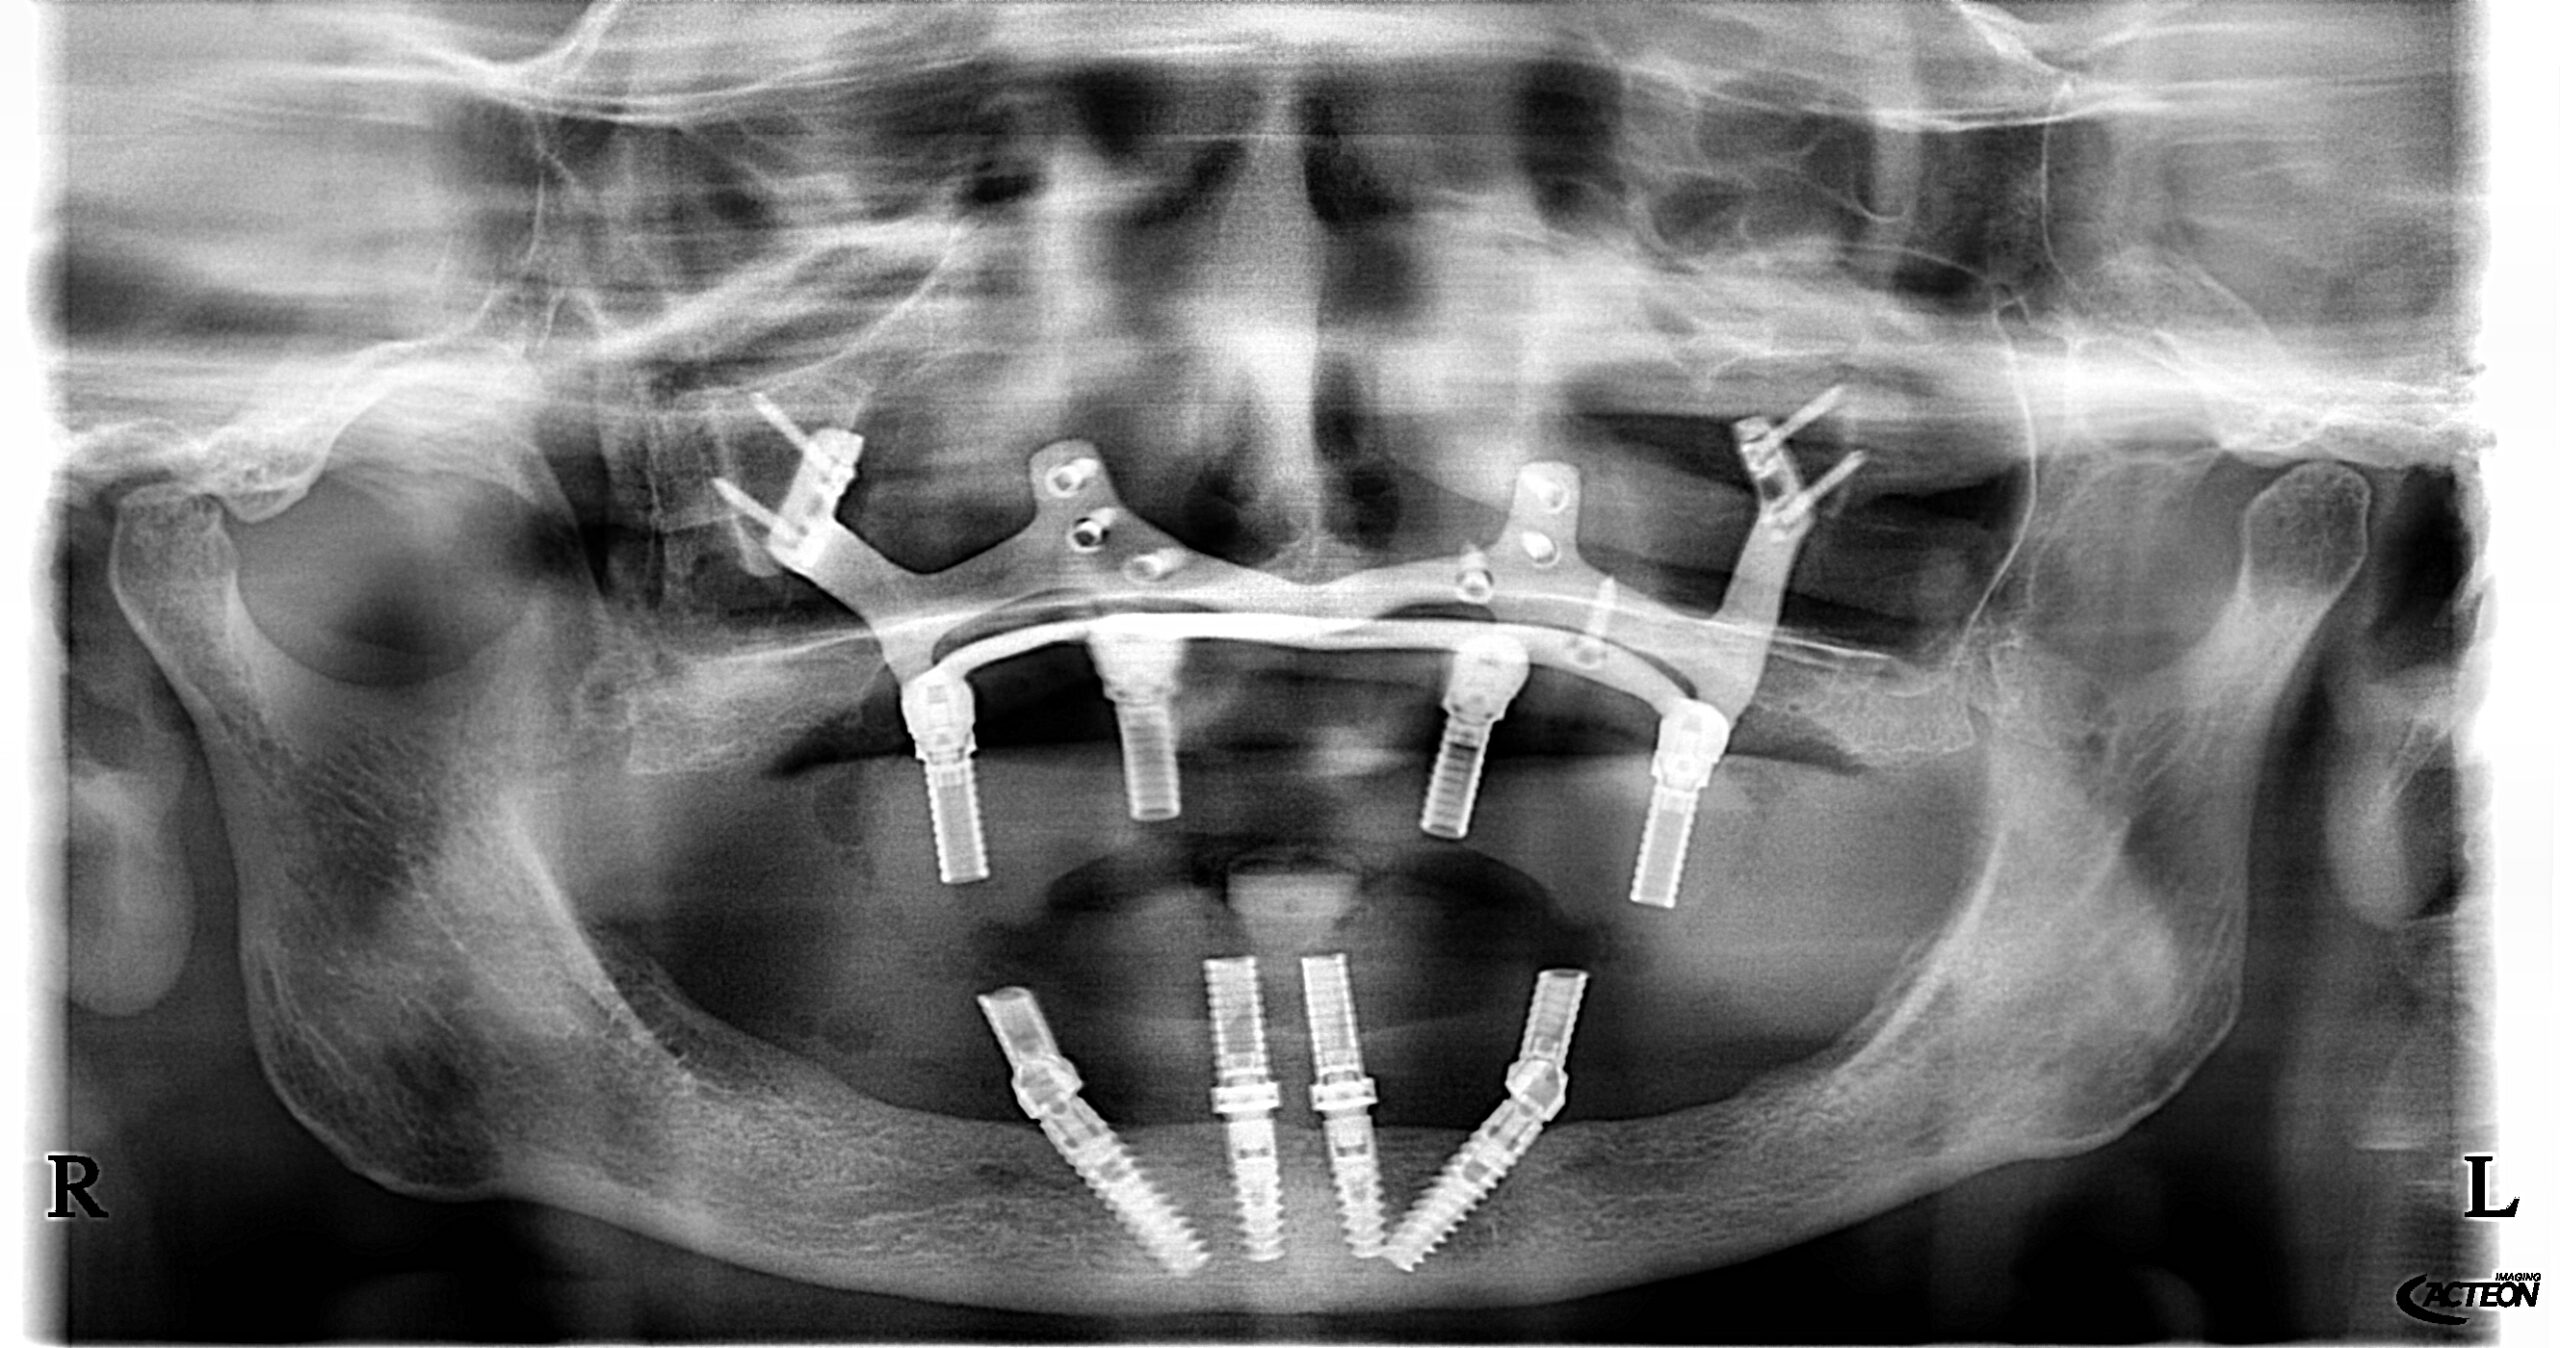

Der Duisburger Zahnarzt Dr. med. dent. Mustafa Ayna ist mit seiner Praxis in der Duisburger Stadtmitte laut portugiesischer Herstellerfirma BONEEASY der erste Anwender einer neuen Methode für Zahnimplantate ohne Knochenaufbau in ganz Deutschland. Die sogenannten »Customize Implants« oder zu Deutsch »Patientenspezifische Zahnimplantate« (kurz: PSI) sind eine alternative Methode mit individuell angefertigten Titankonstruktionen als Bindeglied zwischen Implantat und Kiefer für festen Zahnersatz bei zahnlosen Patientinnen und Patienten, die unter starkem Knochenabbau leiden.

In einem ersten Termin wird mit computertomographischen Aufnahmen die Kieferknochensituation abgebildet. Anhand der Daten kann mit einer speziellen CAD-Software (Computer Aided Design) die Verbindungskonstruktion auf die patientenspezifischen Knochengegebenheiten designt werden. Im Anschluss wird die Titanimplantatkonstruktion per Laserverfahren hergestellt. Der Prozess dauert 2-3 Wochen. In einem weiteren Termin wird die Konstruktion chirurgisch mit Befestigungsschrauben in den Restknochen des Kiefers integriert. Am selben Behandlungstag kann auch die Implantatbehandlung mitsamt Zahnersatz erfolgen. Die Konstruktion ermöglicht den Implantaten sofort einen festen Halt.